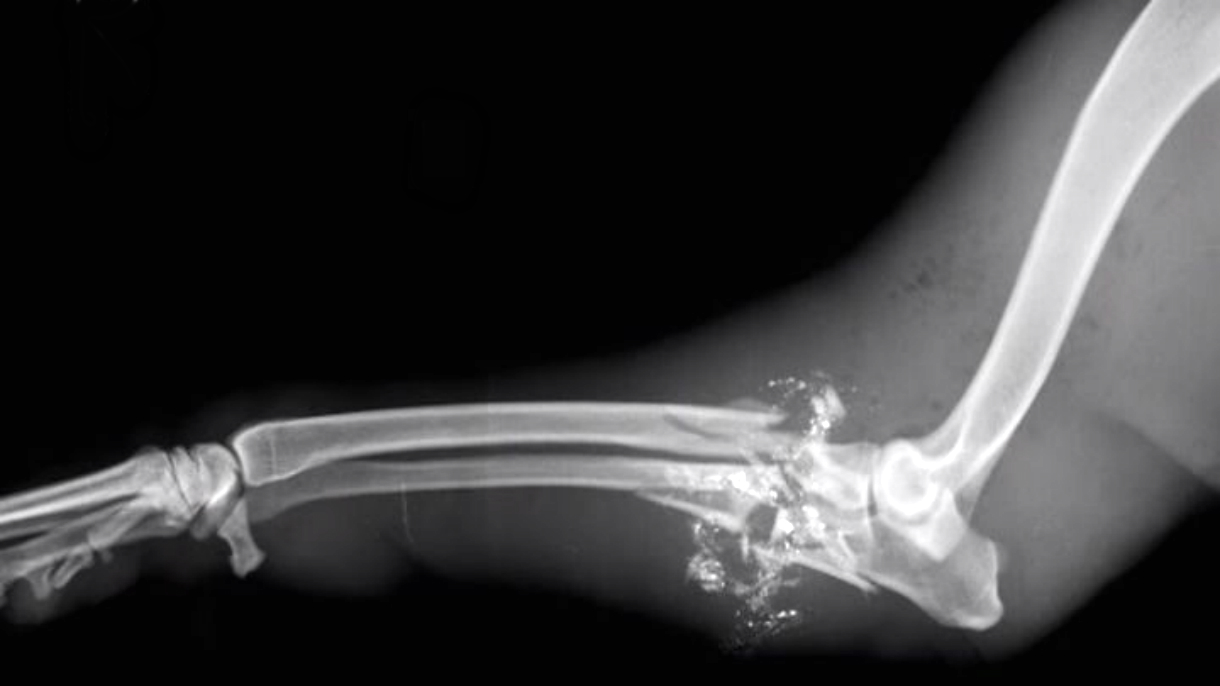

Храбрая собака прикрыла своим телом детей от выстрела убийцы Попытаться подобрать серию (одинаковое название и разные цифры в конце) к этой публикации

Собака по кличке Майра вместе со своими хозяевами спокойно жила в одном из бедных районов Кейптауна, но однажды произошла трагедия.

В дом хозяев проник вооруженный грабитель. Преступник был почти сразу же обнаружен хозяевами и в панике пустил в ход огнестрельное оружие. Чтобы окончательно избавиться от свидетелей, он отправился в детскую…